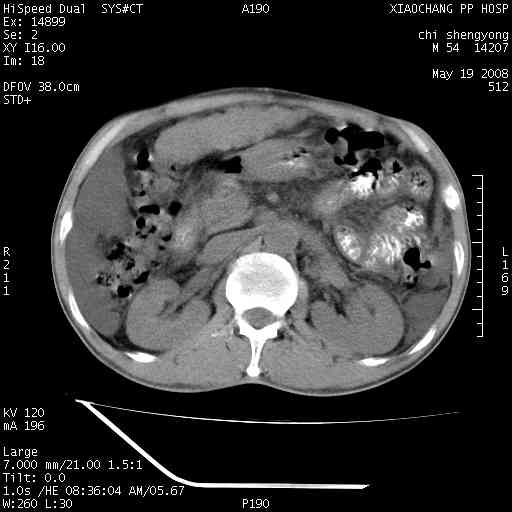

以下是引用zjzjr在2008-5-21 10:52:00的发言:[br]肝左叶巨块型肝癌伴门静脉左支瘤栓形成.肝硬化、腹水,胃底静脉曲张,脾术后改变。

以下是引用随光逐影在2008-5-21 16:20:00的发言:[br]1)肝左叶肝癌伴门静脉左支瘤栓形成,腹膜后淋巴结转移。2)肝硬化、腹水、胃底静脉曲张。3)胆囊炎。4)脾脏缺如,为切除术后所致。